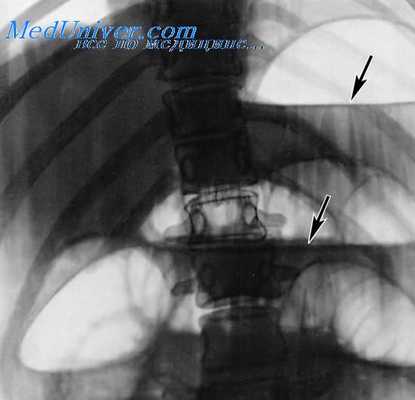

Ведущие рентгенологические признаки тонкокишечной непроходимости хорошо известны: натянутый газом кишечник выше препятствия, наличие чашеобразных уровней жидкости и при полной непроходимости — отсутствие газа ниже препятствия. Наличие параллельной исчерченности, обусловленной утолщенными складками слизистой оболочки и идущей в поперечном направлении по отношению к просвету, весьма характерно для растянутой тонкой кишки.

Рентгенография ОБП при кишечной непроходимости